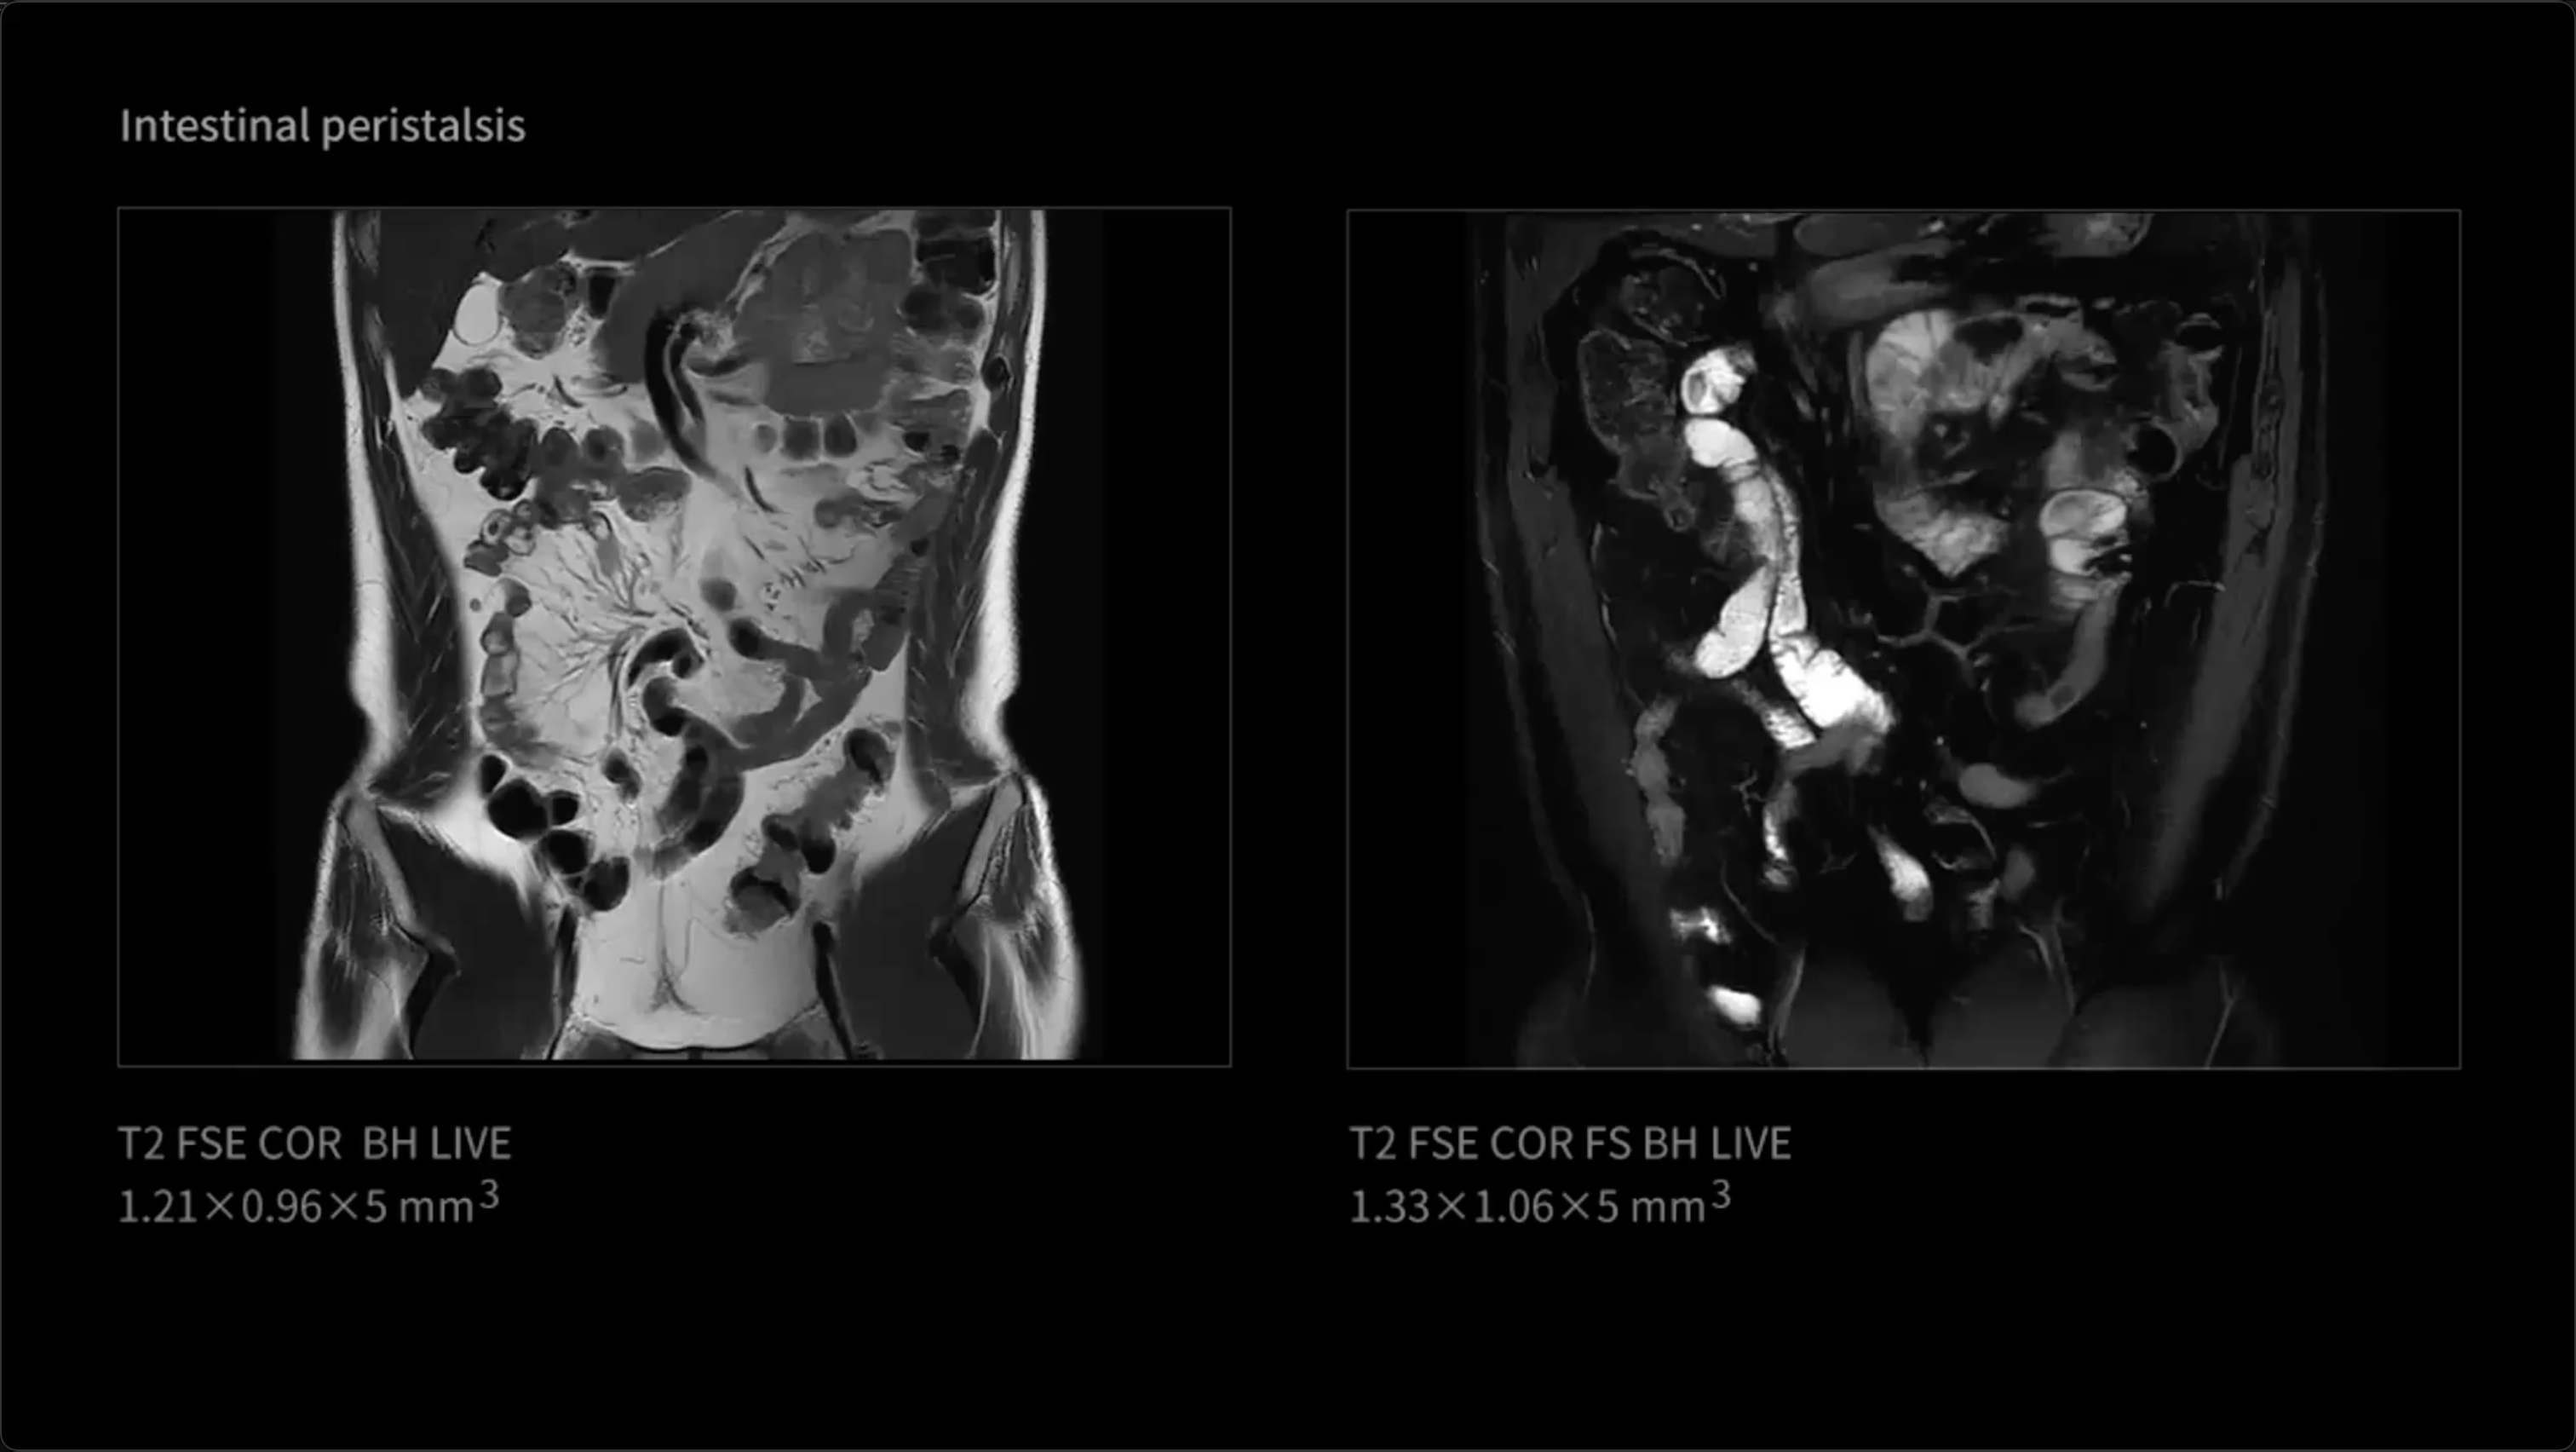

uMR Ultra introduces groundbreaking LIVE Imaging, enabling comprehensive whole-body 'photography' that continuously captures high-definition visualization of both anatomical structures and functional tissue activity. The LIVE Imaging technology not only delivers exceptional frame-by-frame clarity, but also provides coherent dynamic information that unlocks a new diagnostic dimension. This represents significant potential for improved evaluation of dynamic anatomical regions including the gastrointestinal tract, pelvis, joints, and nervous system, among others.